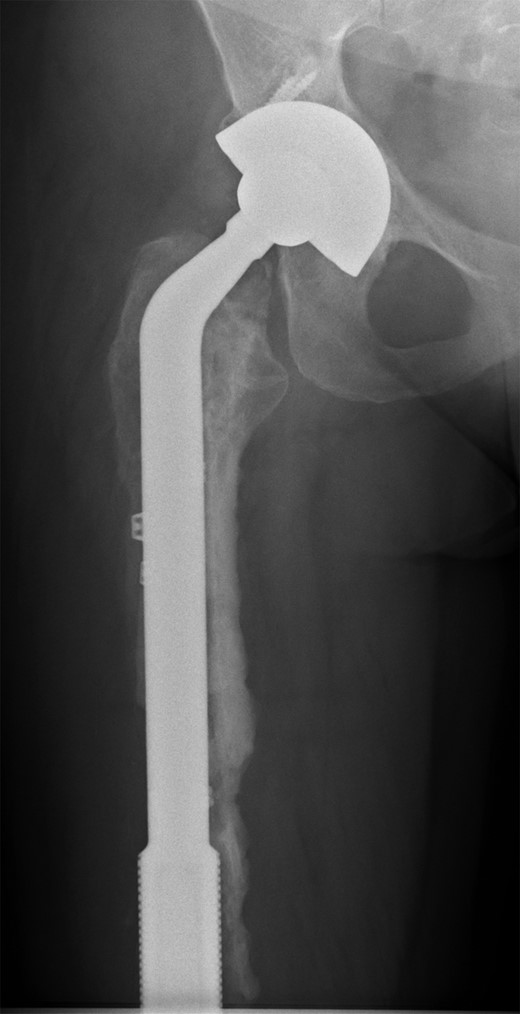

She subsequently sustained a periprosthetic fracture at the distal tip of her right total hip replacement (Fig. 1). An initial attempt was made to manage this fracture with a plate and Dall-Miles cables (Fig. 2); however, the fracture did not unite. The patient went on to have a custom-made cement-linked internal proximal femoral replacement, which had a hollow cylindrical design to accept the stem of the existing well-fixed distal femoral component (Figs 3 and 4). This linked prosthesis effectively converted her separate prostheses to a total femoral replacement, sparing her distal femoral replacement from revision. She had no problems postoperatively and recovered well from her surgery.

Custom-made cement-linked internal proximal femoral replacement.

Existing distal femoral replacement with stem linked to custom-made internal proximal femoral component visible in upper half of the image.